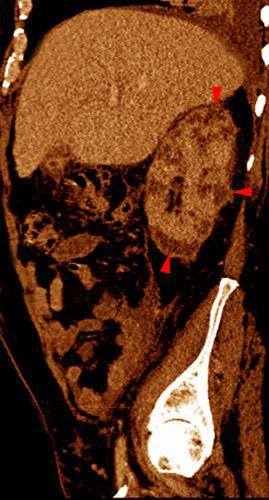

VR seccional. Visión sagital izquierda. Nefromegalia. Múltiples lesiones hipodensas (puntas de flecha) correspondientes a abscesos renales